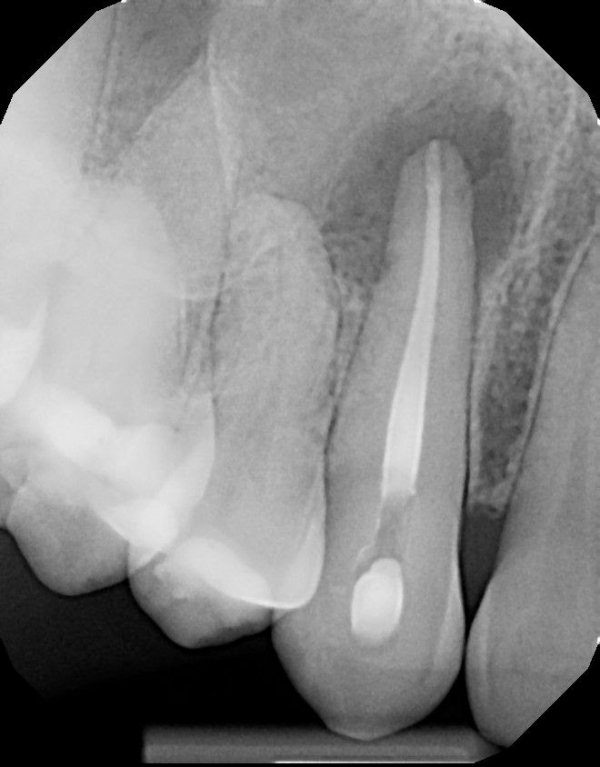

Мой сын случайно головой ударился о мой клык. Боли я почти не чувствовала, но со временем заметила шишечку на десне. Но не сразу придала значения, так как зуб полностью был здоров. Я не знала, что от такого незначительного удара корень зуба может умереть. Врач промыл канал, лекарство поставил всего на две недели, а потом закрыл канал. Чего я не ожидала, делала в другой стране. Шишка со щеки спала, но неожиданно через два почти месяца появилась вновь. За один день увеличилась и лопнула. Пришла к врачу, сделали снимок 3Д. По снимку видно, что уже кости нет. Инфекция распространилась ещё больше, как я понимаю, что уже захватывает соседний зуб. Мне предлагают сделать резекцию корня зуба. Понимаю, что альтернатива - это только удаление зуба. Так как живу в стране, где стоматология ужасно дорогая, и решается вопрос ехать в Россию, чтобы вылечить. Если есть, конечно, смысл.

Резекция верхушки корня может помочь в сохранении зуба, но думаю в связи с таким обширным воспалением зуб все же лучше удалить.

Соседний зуб пока можно попробовать пролечить, путём депульпирования и заведения лекарства за верхушку корня.

Насчёт восстановления кости на 100% никто ничего Вам не скажет. В случае недостаточной костной ткани для имплантации можно сделать ее наращивание остеопластику.